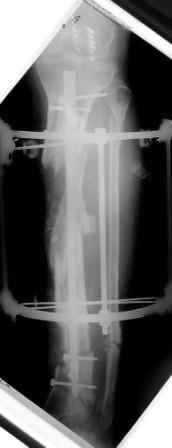

Коллеги!Позвольте продолжить обсуждение темы «ложный сустав левой голени.» Больной К 45 лет, начало см. http://www.weborto.net/forum/1228422607/ И рассказать о результатах проделанной работы. Остановились на следующей тактике 1) Наложить Аппарат Илизарова. В аппарате восстановить оси трех смещенных относительно друг-друга фрагментов большеберцовой кости. Устранить вальгусную деформацию дистального отдела большеберцовой кости. Что и было выполнено. - Была выполнена репозиция в аппарате (рис1) 2) После репозиции более очевидна стала проблема дефекта кости в верхней трети голени, два фрагмента свободно лежат. Остановились на варианте перехода на интрамедуллярный синтез стержнем с покрытием костный цемент+ванкомимцин и замещении дефекта с помощью транспорта фрагмента (рис 2) 3) Третьим этапом наложили модуль на промежуточный фрагмент.(рис 3) И начали его транспорт на стержне в проксимальном направлении. (рис 3 а) Надеемся что «вырастет» регенерат в дистальном отделе, а в проксимальном отделе фрагмент «упрется» и прирастет. Хочу сказать слова благодарности за обсуждение на форуме этого случая. Особые слова благодарности Иванову Павлу Анатольевичу!!! Он помогал Словом, а самое главное делом. Приезжал, оперировал! За что ему нижайший поклон! С ув Коробушкин Г